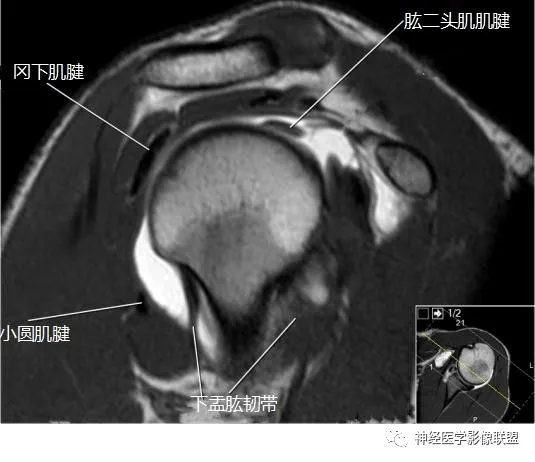

影像解剖肩关节磁共振断层

图片尺寸535x462